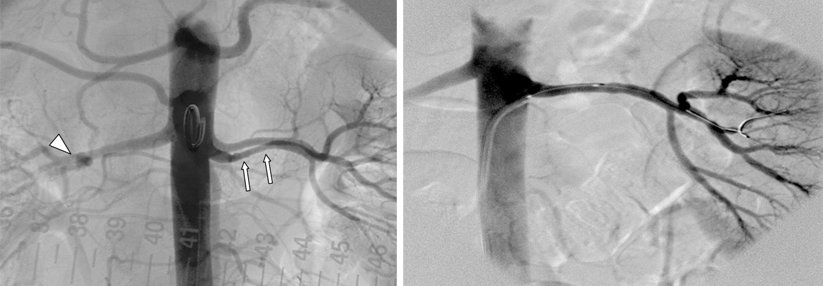

Stenose der Nierenarterie per Revaskularisierung behandeln?

Eine Angioplastie mit Stenteinlage funktioniert bei vielen atherosklerotischen Gefäßen. Doch an der Niere zeigte sie in Studien bisher nur selten…